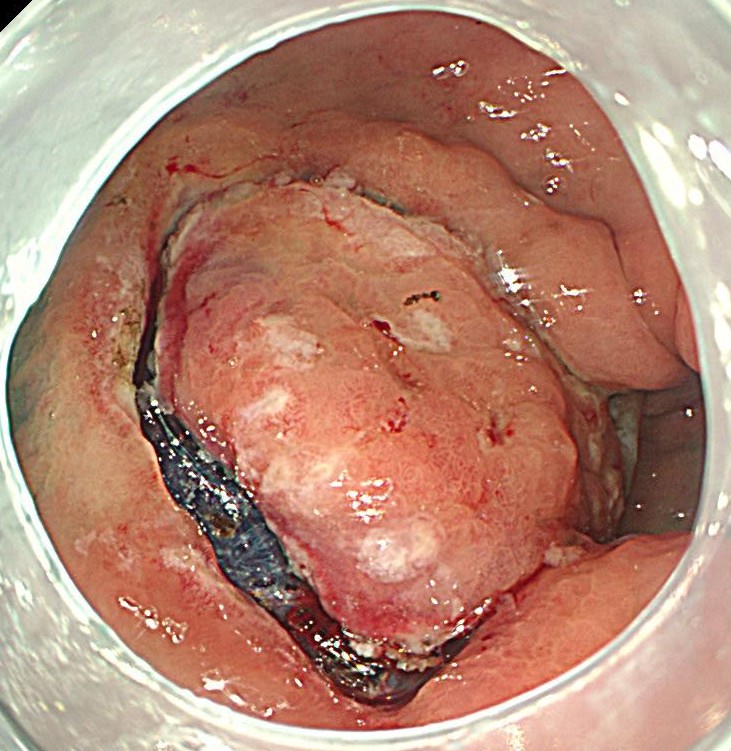

粘膜切除後の欠損部です。この後、1ヶ月間、胃薬を内服してもらいます。

切除標本です。高分化型粘膜内癌であり、根治切除と診断されました。